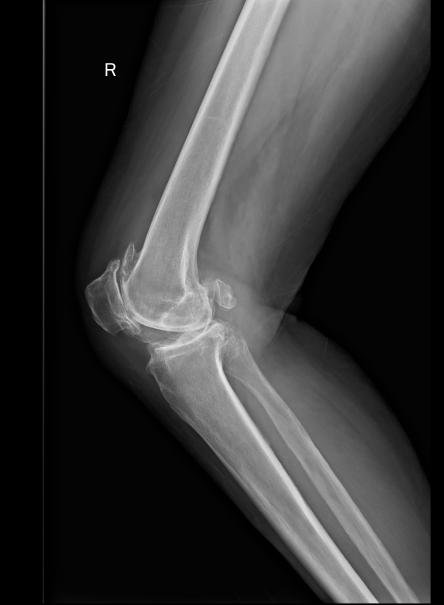

图3a 原发性单侧膝关节炎已至晚期(跛行步态,右膝屈曲外翻畸形,内侧间隙压痛)

图3b 原发性单侧膝关节炎已至晚期(跛行步态,右膝屈曲外翻畸形,内侧间隙压痛)